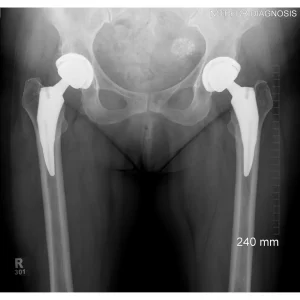

A total hip replacement (also called total hip arthroplasty) is a surgical procedure in which a damaged or worn hip joint is replaced with artificial components. The hip is a ball-and-socket joint, meaning the ball at the top of the thigh bone sits in a socket on the pelvis. During surgery, the damaged ball (femoral head) is replaced with a metal or ceramic ball attached to a stem, and the damaged socket is replaced with a metal cup lined with plastic, ceramic, or metal.

- The surgeon removes the damaged bone and cartilage and inserts the artificial joint

If a hip replacement wears out or loosens, a revision surgery may be required. However, advances in materials and surgical techniques continue to improve implant longevity.